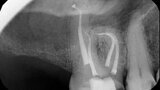

Fig. 14a: Case treated with Bassi Logic controlled memory nickel titanium files. Note the visualization of the third root on this lower molar and conservative canal preparation shape. (Courtesy of Dr. Alex Chan)

Fig. 14b: Case treated with Bassi Logic controlled memory nickel titanium files. Note the visualization of the third root on this lower molar and conservative canal preparation shape. (Courtesy of Dr. Alex Chan)